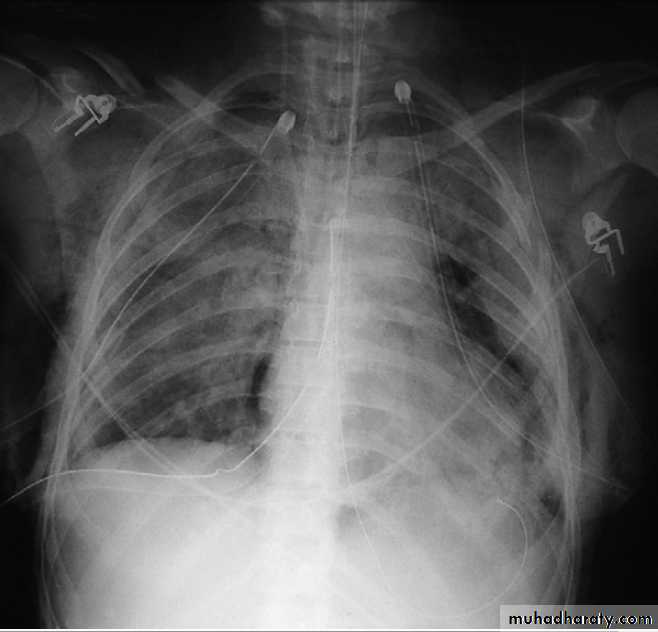

Chest X-ray in acute respiratory distress syndrome

(ARDS). Note bilateral lung infiltrates, pneumomediastinum,pneumothoraces with bilateral chest drains, surgical emphysema, and

fractures of the ribs, right clavicle and left scapula.